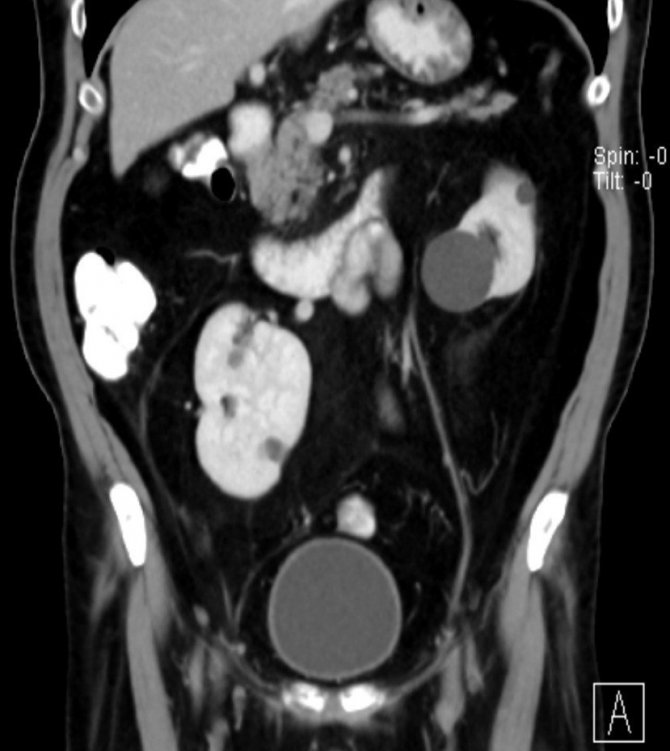

Karın ağrısı ve idrarda kan görülmesi şikâyetiyle, Trakya Üniversitesi Hastanesi Üroloji Polikliniğine başvuran ve yapılan kontroller sonrası sağ böbreğinin çok nadir görülen şekilde karnın alt kısmında, bağırsaklarının arkasında olduğu ve üzerinde bir tümör de olduğu tespit edilen 70 yaşındaki S.K adlı hasta, Trakya Üniversitesi Hastanesi'ne başvurana kadar doğuştan tek böbreği olduğunu bildiğini ve iki böbreği olduğunu öğrendiğinde şaşkınlığını gizleyemediğini belirterek, kendisini tedavi ederek hayata döndüren doktorlara teşekkür etti.

Başarıyla sonuçlanan operasyon, dünyada bir ilk olma özelliği taşıyor. Literatürde, benzer bir vak'a ile 2018 yılında Japonya'da karşılaşıldığı ve oradaki ameliyatın açık tekniklerle yapıldığı bilgisini aktaran Doç. Dr. Hakan Akdere, dünyada ikinci Türkiye'de ise ilk kez böyle bir vak'a ile karşılaşıldığını belirtti. Hastanın sağ böbreğinin, dünyada örneği çok nadir görülen bir yerde olduğunu ve bunun operasyonun önemini artırdığını hatırlatan Doç. Dr. Hakan Akdere, "Lumbal böbrekte tümörü olan bir hastayı, kapalı yöntem ile (laparoskopik) böbreği koruyarak, böbrek damarlarını geçici olarak kapatmadan ve sadece tümoral kitleyi çıkararak başarılı bir operasyonla sağlığına kavuşturup 3. gün hastayı taburcu ettik" dedi. Literatürde, 2018 yılında Japonya'da, lumbal böbrekte kitlesi olan bir hastanın açık teknik ile ameliyat edildiği ve böbreğinin tamamen alındığı bilgisi var. Dünyada daha önce laparoskopik cerrahiyle ilgili yaklaşımların mevcut olduğunu ancak böyle bir vak'ada, bu yöntemle yapılan ameliyatın ilk kez Türkiye'de, Trakya Üniversitesi'nde gerçekleştiğine ve tıp literatürüne geçecek bir yöntemle hastanın sağlığına kavuştuğuna dikkat çeken Doç. Dr. Hakan Akdere, "Böbrek tümörü tedavisinde, kanserli dokunun yayılımına göre böbreğin tamamının veya böbreği koruyarak sadece kitlenin alınması gerektiğini" vurguladı. Bu tür ameliyatları açık, Robotik Cerrahi ya da Laparoskopik cerrahi ile gerçekleştirmek mümkündür. Trakya Üniversitesi Tıp Fakültesi Üroloji A.B.D. olarak, lumbal böbrekte kitlesi olan bir hastayı, dünyada ilk kez "laparoskopik" cerrahi ile sağlığına kavuşturduk. Bu yöntem, bu tür bir vakada ilk kez uygulanan, henüz literatürde yeri olmayan bir başarıdır" ifadelerini kullandı.